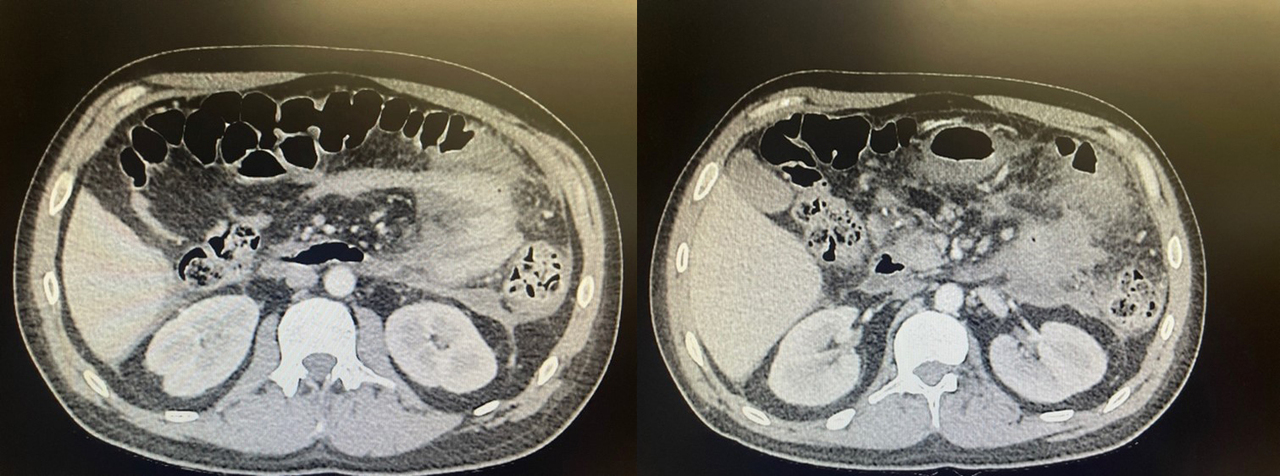

Afin de faire le diagnostic de pancréatite aiguë, il faut une lipase > 3 N.

Afin d’affirmer le diagnostic de pancréatite aiguë, il faut une lipase > 3 N et une douleur épigastrique typique. Le seul examen biologique pour affirmer la pancréatite aiguë est donc la lipasémie. La CRP, la créatininémie et la NFS permettent de rechercher des critères de gravité. La calcémie, le dosage des triglycérides et le bilan hépatique font partie du bilan étiologique de la pancréatite aiguë.